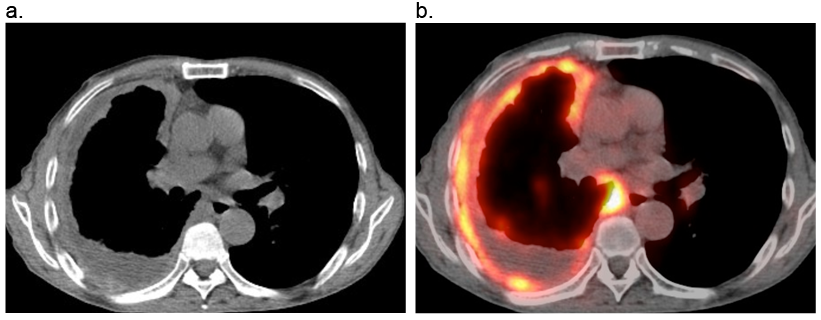

胸膜中皮腫のT2期の特徴的な画像

a:肺を取り囲むような全周性の胸膜肥厚が認められる。

b:FDG-PETでは肥厚した胸膜に陽性所見がみられる。